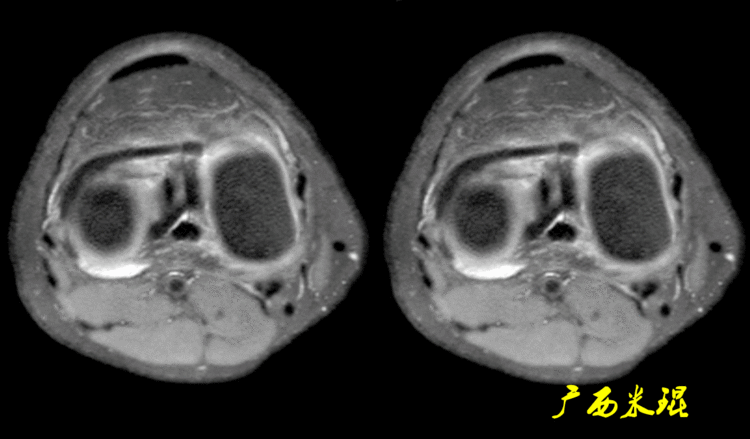

(1)假桶柄MR冠状位上偏后的层面,“C”形或“O”形的内外侧半月板偏后侧层面有可能同时扫描到半月板体部和后角,容易误诊为桶柄状撕裂,而矢状位或横断位上半月板形态是正常的。

下面这张MR冠状位显示为内侧半月板后角的假桶柄,其母体(图片中内侧的那一部分半月板)并没有变小、形态及信号均正常。

下面这张MR冠状位显示为外侧半月板后角的假桶柄,尽管在髁间窝发现半月板信号,但其母体(图片中外侧的那一部分半月板)并没有变小、形态及信号均正常。